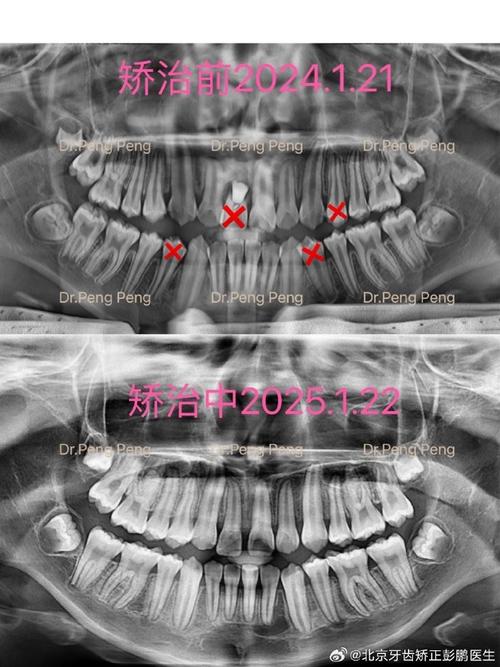

- 影像学检查: 拍摄根尖片是评估牙根长度和形态的金标准,必要时拍摄曲面断层片或CBCT(锥形束CT)进行更全面的评估和基线记录,CBCT能更精确地测量牙根长度和发现早期吸收。

- 定期影像学复查: 这是最重要的监测手段! 通常在治疗开始时(基线)、治疗中(如6个月、1年)以及治疗结束时拍摄根尖片,对于高风险病例或进行显著压低移动的牙齿,可能需要更频繁的复查(如每3-6个月一次),CBCT可用于更精确的测量和早期发现微小吸收。

- 治疗结束时的根尖片: 与基线片对比,评估牙根长度的变化。

- 诊断: 主要依靠根尖片(观察牙根轮廓、长度变化)和CBCT(精确测量吸收量、位置、范围),临床检查(松动度、叩诊、活力测试)作为辅助。